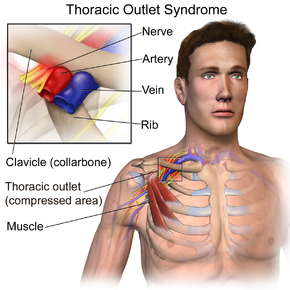

この状態で運動を続けていくとどんどん痛みが出やすい体になるのと、小胸筋の間を通っている神経や血管を圧迫してしまいます。

これを改善、予防するためには正しい肩の位置を作りながらの小胸筋のストレッチが必要です。

雑誌などでこのストレッチ方法が載っていますが、より専門的に考えると残念ながら、肩甲骨を前側に傾かせないように、お一人で行う方法はなかなかむずかしいのが現状です。